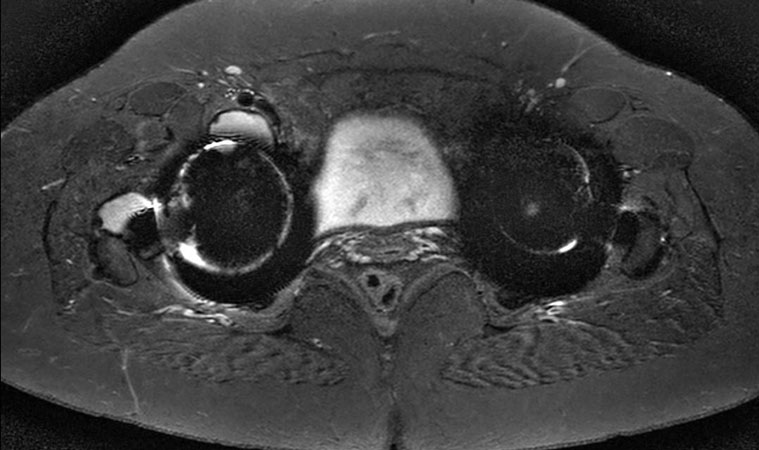

Axial STIR TSE